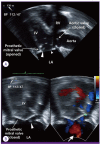

Abiotrophia defectiva, a nutritionally variant streptococci can cause bacteremia, brain abscess, septic arthritis and in rare cases, infective endocarditis, which accounts for 5-6% of all cases. A. defectiva is characteristically difficult to diagnose and the mortality, morbidity and complication rates are high. Here, we discuss a case of infective endocarditis caused by A. defectiva. A 62-year-old female had previously undergone prosthetic valve replacement 6 years prior to admission. She developed infective endocarditis after tooth extraction. Her endocarditis was successfully treated with antimicrobial therapy and mitral valve replacement surgery. This is the first case of infective endocarditis caused by A. defectiva reported in Korea. This case shows that A. defectiva could be considered as a causative organism of infective endocarditis in Korea.